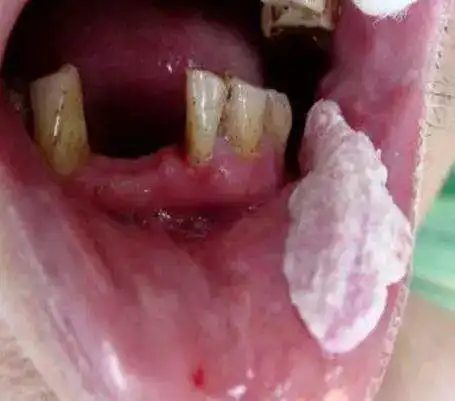

小伙每天4包槟榔酿成大祸 医生提醒:谨防口腔癌

据统计,90%以上的口腔癌 都与槟榔相关 口腔癌的前身 就是口腔黏膜

槟榔是目前已经得到世界卫生组织证实的一级致癌物,主要导致口腔癌.

我是口腔医生我真心希望大家千万不要再吃槟榔了

惠州男子一天嚼两包槟榔竟诱发恶性口腔癌

为什么槟榔会导致癌症,特别是口腔癌呢?